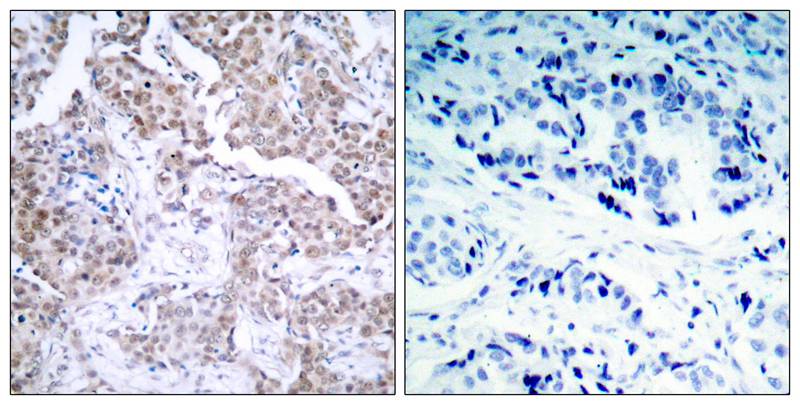

分类: 科研抗体货号: P40070别名: ER; ESR; ESR1; ESTR; ESTRA应用: WB,IHC,IF反应种属: Human,Mouse,Rat